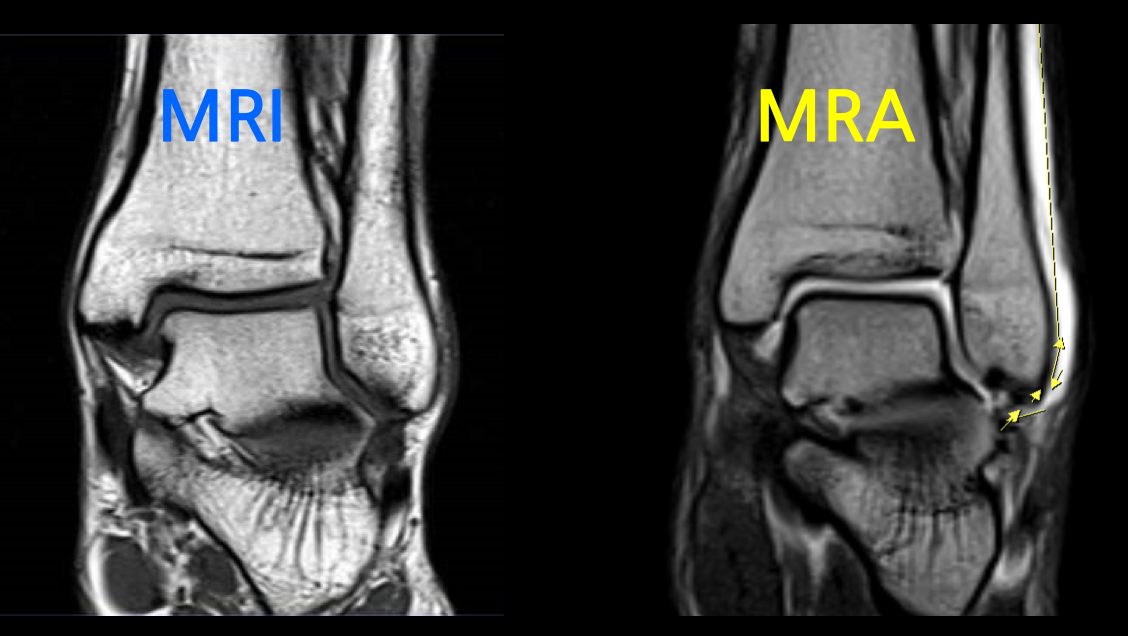

병원 진료 시 체내의 병변 유무와 그 위치 등을 알기 위해 정밀검사가 필요합니다. 관절, 혈관 등 어떤 조직이냐에 따라 MRI 또는 조영제를 이용한 MRA(Magnetic Resonance Arthrography/Angiography)를 촬영하며, 어떤 차이가 있는지 알아보도록 하겠습니다.

MRA는 MRI와는 다르게 조영제를 사용하며 특히, 같은 부위를 촬영하더라도 조영제 유무에 따라서 촬영된 영상 이미지에 큰 차이가 존재합니다.

작고 좁은 관절에 연부조직을 확인하기 위하여 조영제를 사용하며, 손상여부 및 정도를 확인할 수 있습니다.

어깨, 팔꿈치, 발목 관절에 조영제를 주입하여 MRI를 촬영하면 조영제가 손상된 틈으로 스며들어 관절 속 미세한 병변까지 진단할 수 있습니다. 이를 관절조영증강 MRI 또는 MRA(Magnetic Resonance Arthrogram)이라고 부릅니다.